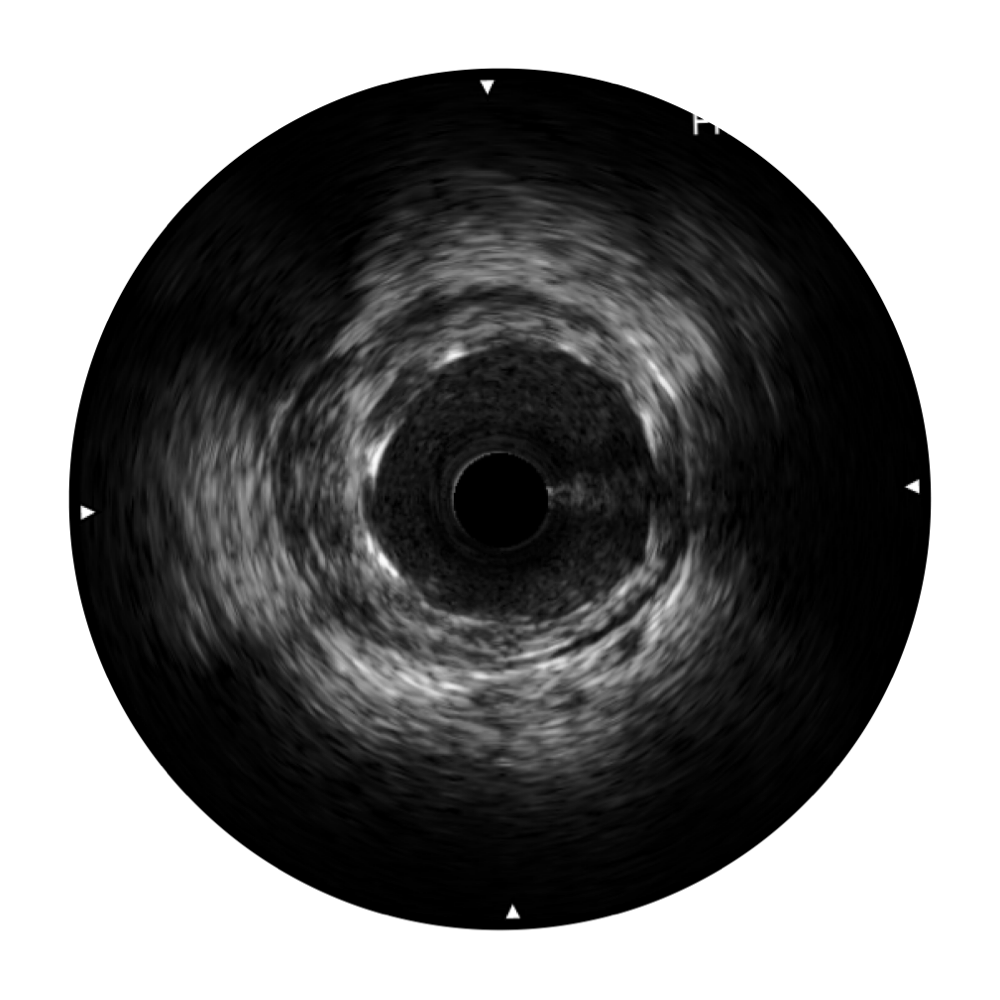

開(kāi)立寬頻IVUS圖像

傳統(tǒng)IVUS圖像

對(duì)比傳統(tǒng)IVUS導(dǎo)管成像,開(kāi)立寬頻IVUS圖像的近場(chǎng)支架梁顯影更細(xì)膩,遠(yuǎn)場(chǎng)中膜外血管仍清晰可辨,兼顧遠(yuǎn)中近,兼顧分辨力與穿透深度